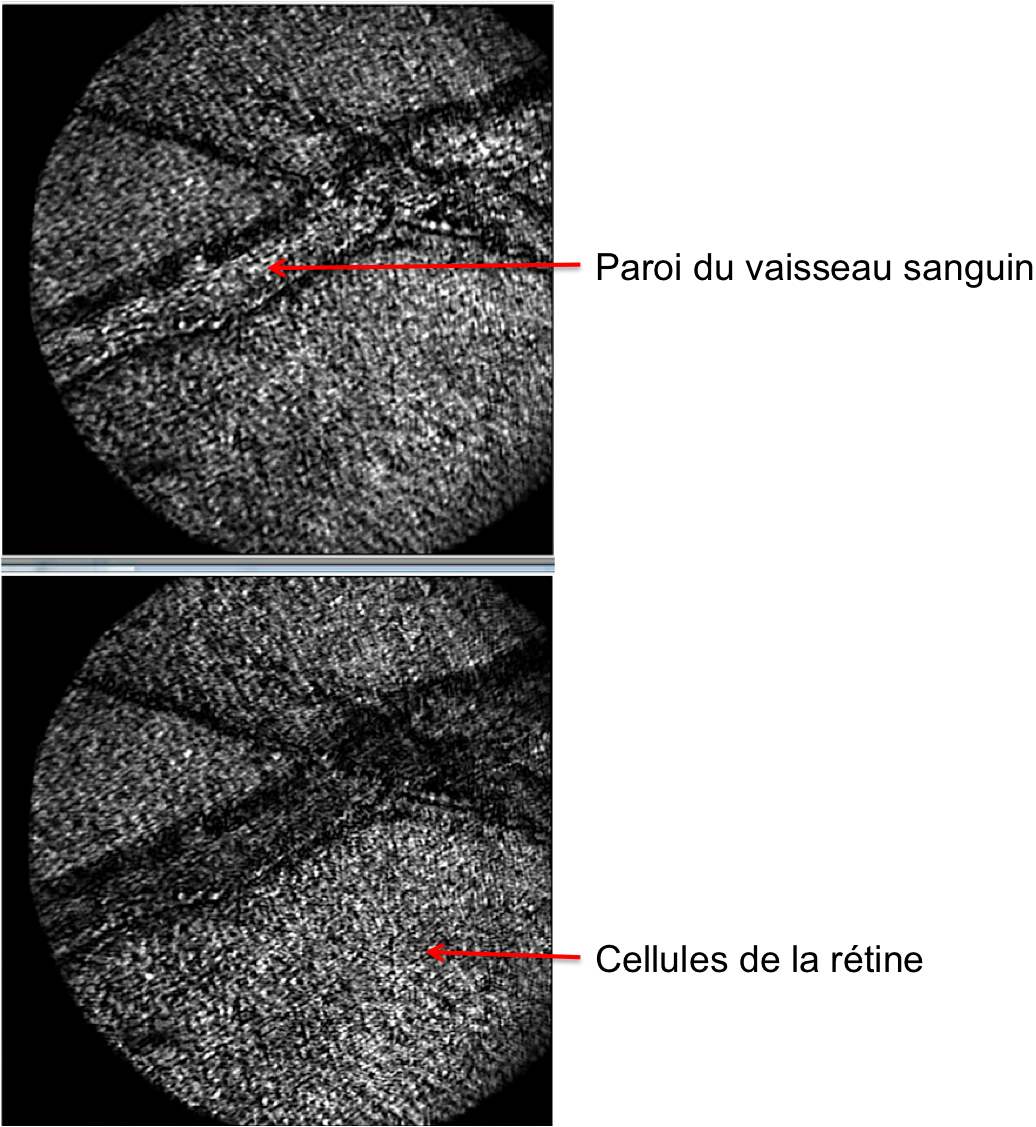

Des images de rétines explantées de rat, entre lame et lamelle, ont été obtenues sur le banc d’OCT plein champ seule. Après acquisition d’une pile d’images en-face (en XY), n’importe quelle coupe axiale (XZ ou YZ) peut être extraite des données.

Des images OCT de rétines de porc ex vivo ont été obtenues. On observe différentes couches.